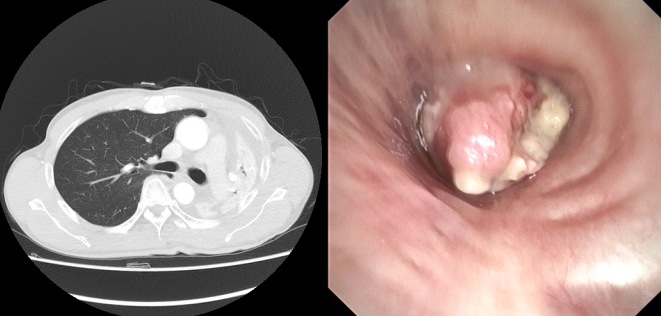

治疗后:CT影像及气管镜下所见

治疗后,多数患者呼吸困难的症状能够得到缓解,肺部复张,生活质量显著提高。尤其对于肿瘤所致气道狭窄的患者,介入治疗不仅能缓解症状,还可为后续治疗创造条件。